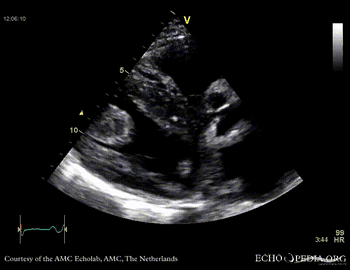

Thrombus in the left ventricle

J. Vleugels, AMC, The Netherlands